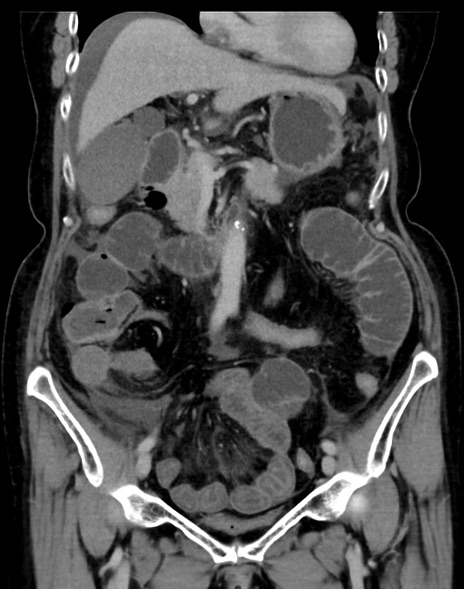

症例13 CT(冠状断像)1日半後